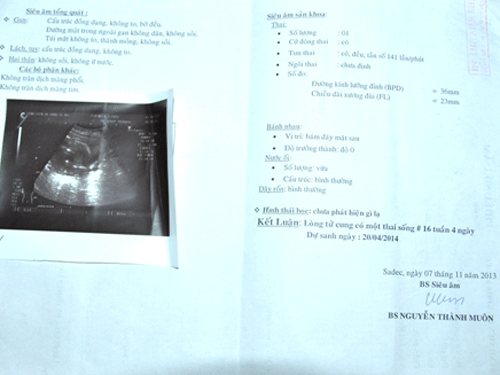

Ngày 13/8, chị N.T.N.D. (SN1984) ngụ ấp An Hòa, xã An Hiệp, huyện Châu Thành, Đồng Tháp nghi đang có thai nên đến Bệnh viện Đa khoa Sa Đéc siêu âm và được bác sĩ kết luận thai ngoài tử cung.